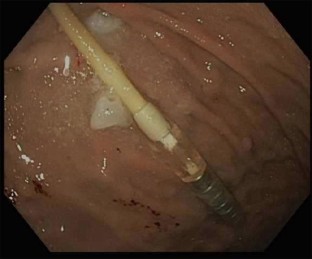

Fig. 3